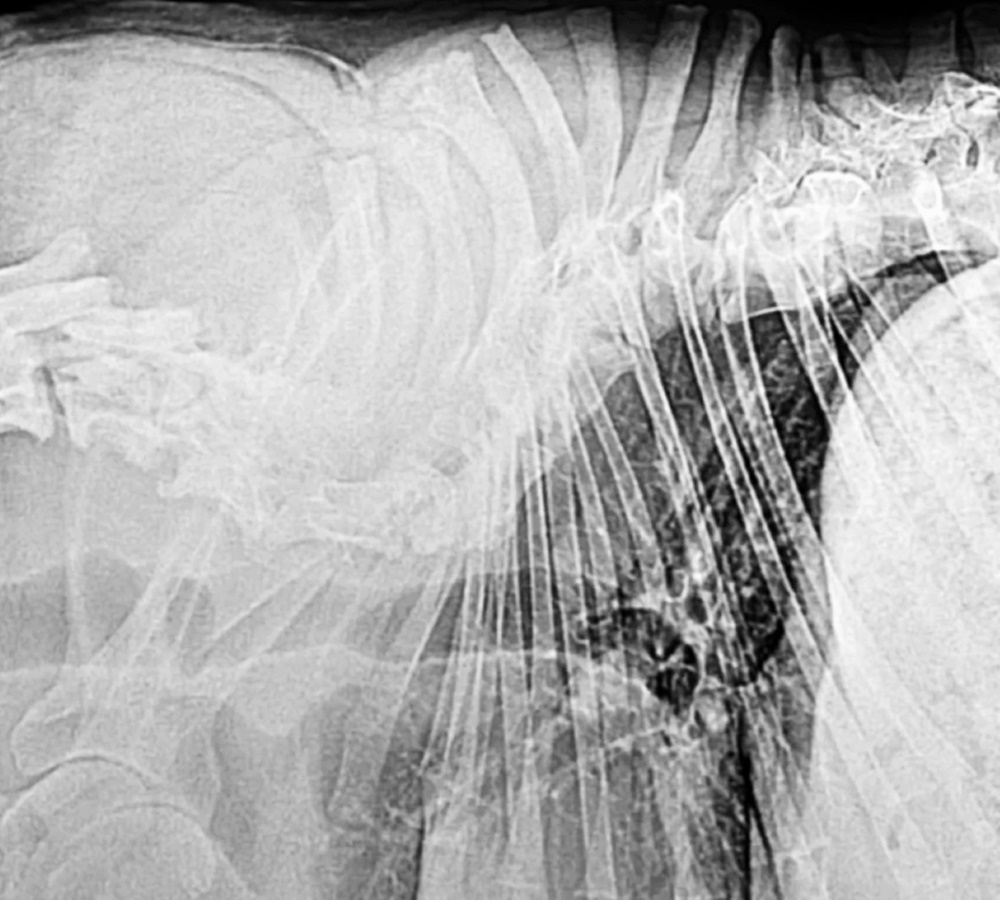

사실 콰지모도는 지난 2016년 1월 SNS 상에서 유명세를 얻었습니다. 콰지모도는 저먼셰퍼드 종인데요. '짧은 척추 증후군(short spine syndrome)'이라는 질병을 앓고 있었습니다. 이 증후군은 전 세계에서 불과 14마리의 강아지만이 보고되었을 정도로 희소한 질병이죠.

콰시모도는 이 질병으로 인해 주인에게 버림받았는데요. 이에 한 동물보호소에서는 콰시모도를 구조했고, 정밀 검사와 치료를 받게 되었습니다. 당시 동물보호소에서는 콰시모도의 자체 페이스북 페이지를 만들었는데요. 단기간에 2만 5천 명이 넘는 팔로워가 생기는 등 엄청난 응원의 물결이 일었습니다.